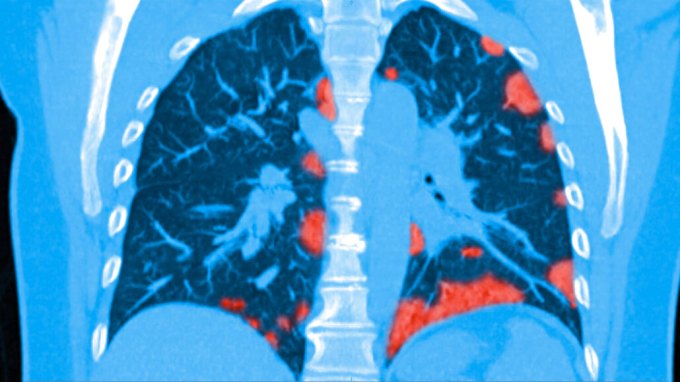

The Coronavirus Pandemic

The latest research and developments on COVID-19 and SARS-CoV-2, the novel coronavirus behind the 2020 global pandemic.